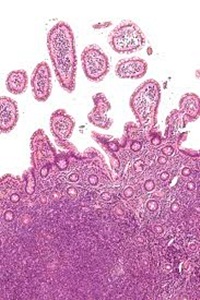

1. 다발성 골수종

골수종은 다발성 골수종 또는 형질 세포종이라고 불립니다. 골수종은 뼈에 침투하는 특징이 있고 뼈를 녹이기 때문에 골절이 잘 일어납니다. 뼛속의 칼슘이 혈액으로 녹아들기 때문에 고칼슘 혈증이 일어날 수 있습니다. 탈수와 피로, 무력감 등의 증상도 나타납니다. 이것은 골수암의 대표적인 증상으로 뼈 손실과 감염 퇴치 능력의 감소로 이어질 수 있습니다.